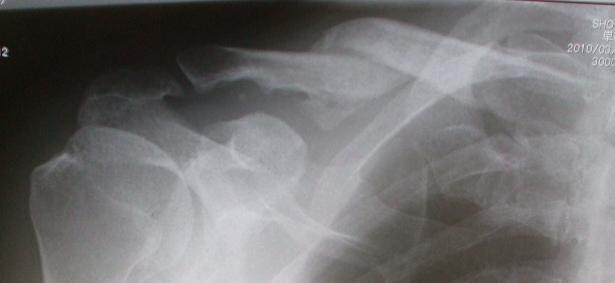

診察の前にレントゲン撮影をしましたが、CTによる断層ではないので骨の融合は不明ですが、先生の弁では「繊維性の付着であろう」とのこと。そして、ここで、改めて手術はせずに、一旦、治癒となりました(写真)。

骨は重なりあっているように見えるのですが、重なりの部分だけ左に比べ右は肩幅が狭いことになります。